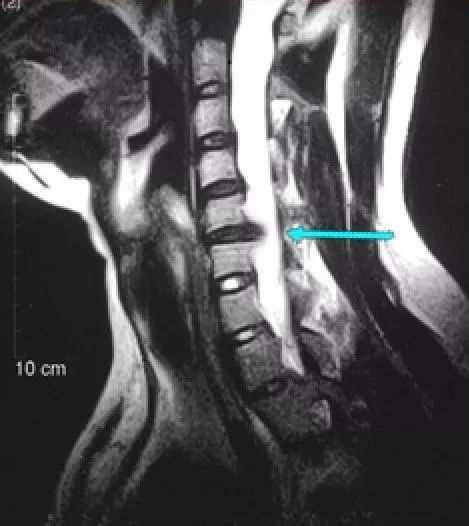

颈椎间盘突出患者的MRI示意图,可以清晰的看到脊髓受到了严重的压迫。